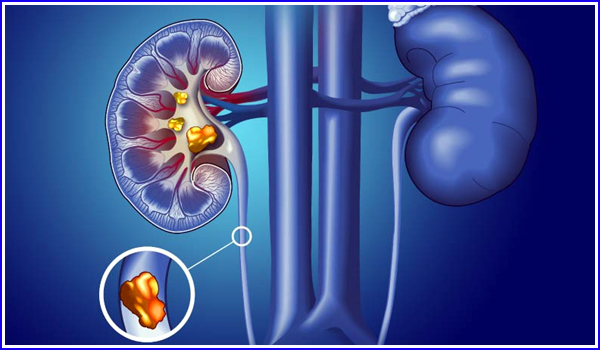

گردے کی پتھری یا گردے کی پتھری کا مسئلہ جسم میں اس وقت ہوتا ہے جب بہت زیادہ فضلہ یعنی فضلہ آپ کے خون میں جمع ہو جائے۔ اس صورت میں، آپ کا جسم کافی پیشاب کرنے کے قابل نہیں ہے. اس سے آپ کے گردوں میں کرسٹل بنتے ہیں۔ اور رفتہ رفتہ یہ کرسٹل اپنے جیسے دوسرے فضلے کے ساتھ گھل مل کر پتھر بننے لگتا ہے۔ وقت کے ساتھ، ان کا سائز بڑا ہو جاتا ہے.

کم پانی پینے کی عادت، موروثی پتھری ہونے کا رجحان، بار بار پیشاب کی نالی میں انفیکشن، وٹامن ‘سی’ یا کیلشیم والی ادویات کا زیادہ استعمال، بستر پر طویل آرام، ہائپر پیراتھائرائیڈزم سب سے زیادہ دیکھنے میں آنے والی وجوہات ہیں۔ اس کے علاوہ یہ مسئلہ موٹاپے کے شکار افراد اور آنتوں کی سرجری کروانے والے مریضوں میں سب سے زیادہ ہوتا ہے۔